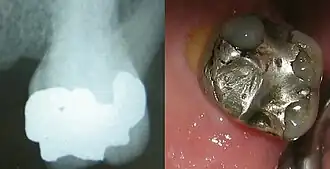

Amalgame dentaire

En dentisterie, un amalgame dentaire est un matériau utilisé pour obturer les cavités résultant de l'élimination de tissus dentaires affectés par des caries.

La composition varie selon les types d'amalgames et les époques.

Un amalgame traditionnel est formé d'un mélange de mercure liquide (1 gramme environ par amalgame) et d'autres métaux en poudre :

- mercure : permet la plasticité du matériau lors de sa mise en place ; il représente 50 % de la masse ;

- argent : c'est le métal majoritaire après le mercure (30 % de la masse) ;

- cuivre ;

- étain ;

- zinc (pas toujours présent) ;

- autres métaux : ils sont ajoutés par les fabricants, mais non révélés (secret de fabrication) pour améliorer le temps de prise ou les propriétés mécaniques finales du mélange. Certains amalgames contiennent du béryllium (métal toxique et très réactif), du palladium, de l'indium ou du platine[5].

Ce mélange conduit à un matériau final très performant pour obturer les dents cariées. Le pourcentage de mercure dans les nouveaux alliages descend à 40-45 %.